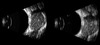

Desprendimiento vítreo postrerior

Desprendimiento vítreo posterior

Hemorragia vítrea

Hemorragia vítreo retiniana